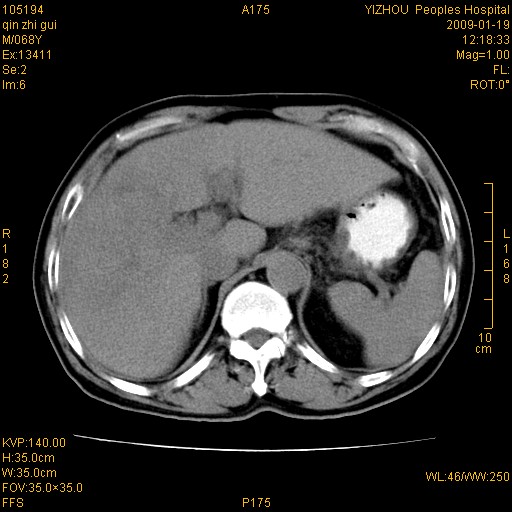

以下是引用随光逐影在2009-1-21 16:11:00的发言:[br]1)考虑肝右叶肝癌并肝静脉及门静脉瘤栓形成。2)肝硬化,少量腹水。3)胆囊炎。4)右侧少量胸腔积液。

病灶外缘凹凸不平,平扫低密度,增强动脉期有强化,门脉早显,静脉期及延期呈延迟强化,结合病史考虑右肝前叶巨块型肝癌可能性大,强化表现不除外胆管细胞癌